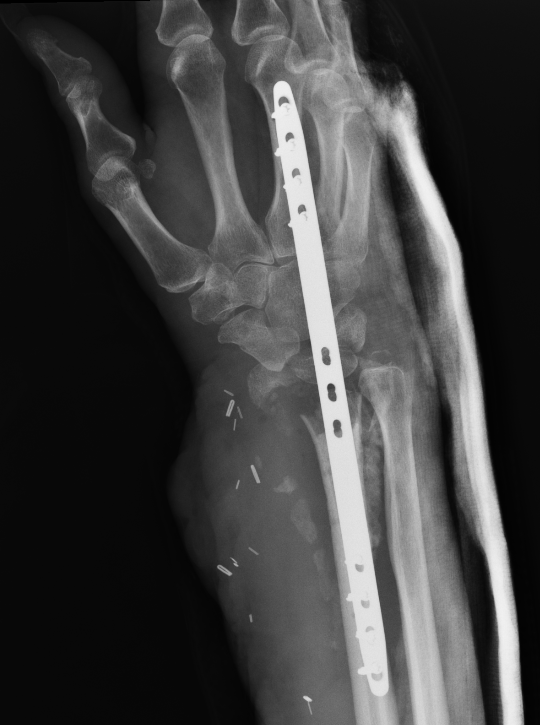

Malunion

www.boneschool.com/distal-radius-fracture-malunion